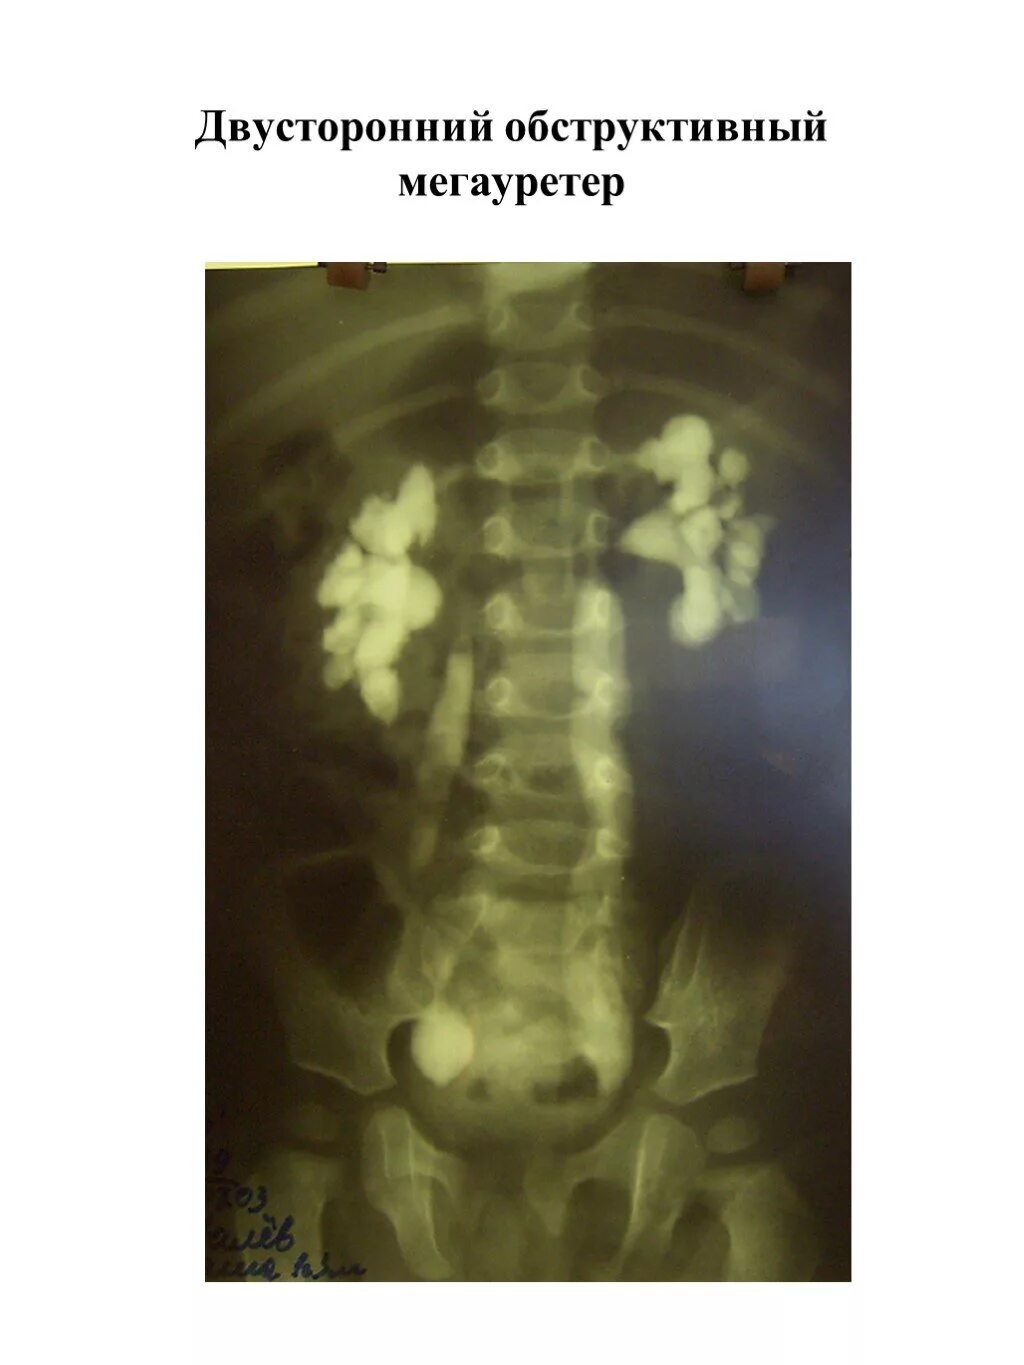

Мегауретер у детей что это